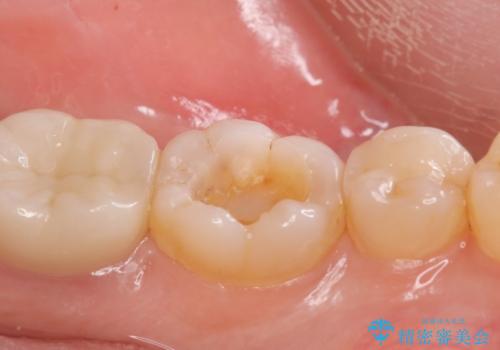

劣化して黒くなりたくない、虫歯の予防がしたいとのご希望だったのでセラミックインレー(e-maxインレー)による治療を行いました。

プラスチック樹脂は安価で治療時間も一回で終わるが歯質との隙間ができやすく虫歯の再発のリスクが高いです。また、吸水性なので何年か過ぎると劣化します。

セラミックは歯質との隙間ができにくく虫歯の再発のリスクをさげ劣化防止にもなります。